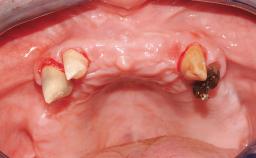

Immediate Loading of Four Implants in the Mandible and Final Restoration with a Full-Arch Metal Framework FDP

Pedro Tortamano, Luiz Otávio Alves Camargo

A fully edentulous 65-year-old woman was referred to our clinic for esthetic and functional dental rehabilitation. The patient presented with inadequate complete maxillary and mandibular prostheses, insufficient vertical dimension, and extensive tooth wear. The clinical examination and anamnesis showed no local or systemic contraindications, no signs or symptoms of bruxism, and an absence of smoking habits. The treatment proposed was implant placement in the mandibular interforaminal area and immediate loading with a fixed definitive prosthesis. A removable mucosa-supported complete prosthesis was indicated for the upper jaw, since its bone structure offered satisfactory retention and the financial condition of the patient disfavored a full-mouth implant-supported rehabilitation.

Case Type Edentulous Mandible

Jaw Mandible

Area Full-Arch